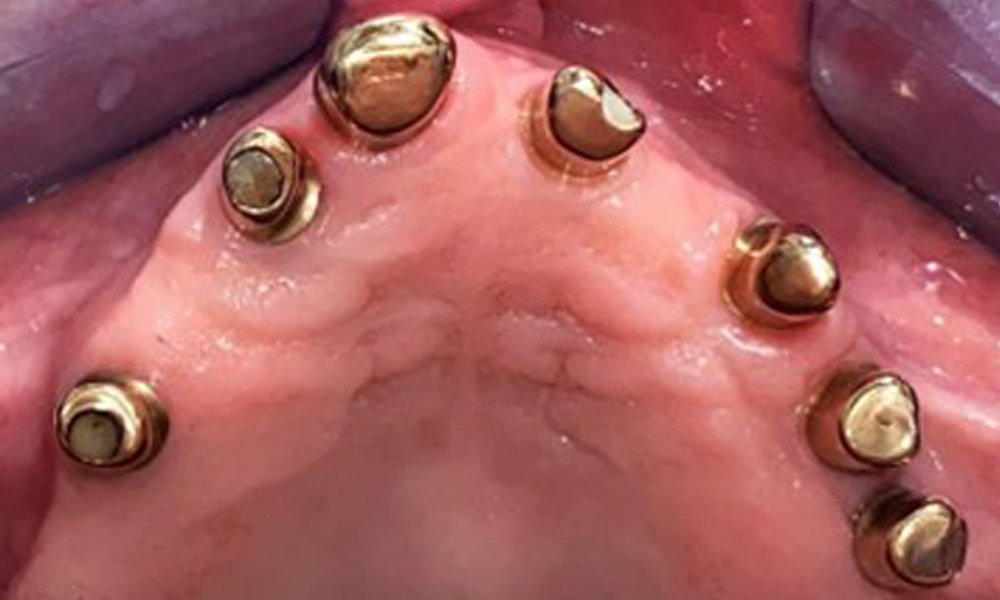

Occlusal view: Maxilla with tooth and implant-supported telescopic prostheses.

Fig. 2: Occlusal view: Maxilla with tooth and implant-supported telescopic prostheses

The dental findings are as follows: Combined removable implant and tooth-supported telescopic prostheses on implants 15, 13, 21, 23, 24, 25 and tooth 11 (Fig. 1, Fig. 2, Fig. 3). The patient was fitted with a fixed mandibular denture. Adequate bridges were present over 37 to 34 and 45 to 47 (Fig. 4), the crown margins were intact and there were no active caries. A composite filling with a marginal gap was present on tooth 43. There was mandibular gingival recession, exposing 1 to 3 mm of root surface. This also applies to 11.

The patient was fitted with a combined removable maxillary telescopic prosthesis more than 25 years ago (Fig. 1, Fig. 2, Fig. 3) and is very happy with her dentures. The patient has an adequate fixed denture for the mandible (Fig. 4).